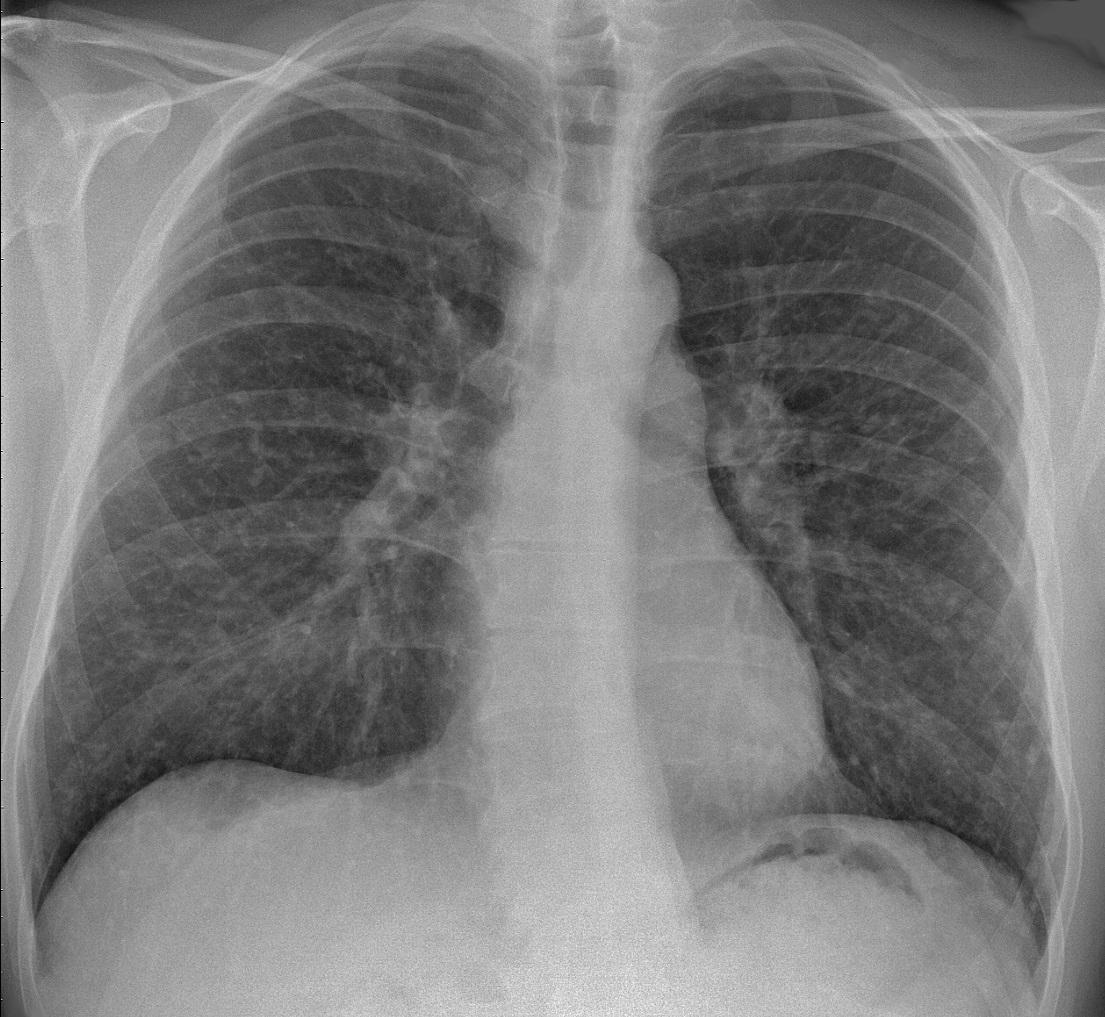

【肺サルコイドーシス】wikipedia

肺胞の薄い壁の中(間質)に毛細血管が走っており、ここでガス交換が行われている事は承知の通りです。この薄い肺胞壁そのものに炎症や損傷が発生し、段々と壁が厚く硬くなって(線維化して)、ガス交換がうまく出来なくなるのが間質性肺炎という病気です。また、肺胞壁ばかりか、小葉間隔壁や、肺全体を包む胸膜壁にも線維化が起こって重篤な肺炎症状を呈してきます。間質性肺炎の原因は様々ありますが、その中でも全く原因が分かっていない間質性肺炎の事を「特発性間質性肺炎」と呼んでおり、国の特定疾患に分類されています。特発性間質性肺炎もパターンが異なる幾つかの種類があって、ここでは「急性・亜急性間質性肺炎」の中から全く原因が不明な「特発性器質化肺炎(COP)」と「急性間質性肺炎(AIP)」に関する知見を述べようと思います。「特発性器質化肺炎」に関しては宇宙医療団にも数例の症例があって、その根本原因は土壌バクテリアの一種であるシュードモナス属の菌類で、その癌化種が放出した発信器によって引き起こされています。近年は農薬を使わない家庭菜園が人気なのですが、事故原発が吐き出す放射性のRADガスが畑に降り積もって、無害な筈の土壌細菌が癌化するケースが増えている様です。

【特発性肺線維症】wikipedia